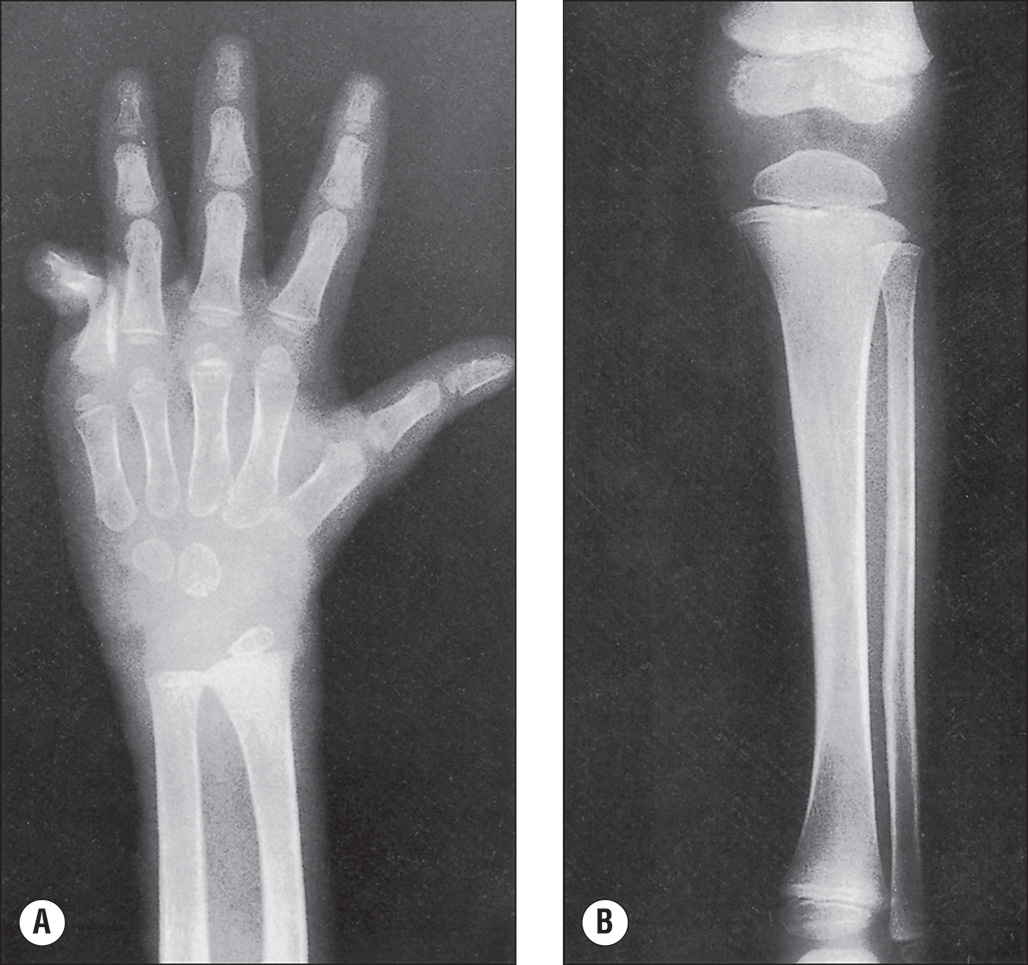

The more extensive the burn and the greater the number of complications, the longer the patient may be confined to bed and relatively immobile. The onset of osteoporosis is accelerated, and its intensity is more marked in the burn illness that features a hypermetabolic state. Klein et al. found that osteoblasts and probably osteocytes underwent apoptosis in response to the glucocorticoid stress hormones. The overall effect of burn is catabolic, and muscle wasting is also noted. If a single extremity of an otherwise normal person is immobilized for a long time because of local trauma, as with a fracture, loss of bone density can be easily seen on plain radiographs. So, with burns isolated to the extremities, the bones of affected extremities become osteoporotic, and in persons with generalized burns, the bones of deeply burned extremities may show more profound mineral loss than is observed in nonburned extremities or in the axial skeleton ( Fig. 41.1 ). This tendency for more osteoporosis in severe burns was also noted by Pandit et al., who found that 56% of postburn patients had radiographic evidence of osteopenia. Van der Wiel et al. found in an x-ray absorptiometry study of 16 adults with fractures of one tibia that there was eventual loss of bone mineral density in the contralateral femur and in the lumbar spine but to a lesser degree than in the ipsilateral femur. These findings, although not strictly analogous to those observed in burns, nevertheless point to the occurrence of generalized osteoporosis in other trauma states and the difference in loss of bone density relative to local factors. In fractures or in burns, impaired mobility and local hyperemia could account for this difference.

(A) At 6 months after injury, the coarsened trabeculation of marked osteoporosis of bones is evident on the left hand and forearm of a 4-year-old boy whose 70% full-thickness burn involved the head, chest, and both upper extremities. (B) A radiograph of the left tibia and fibula obtained on the same date as that of the hand shows minimal atrophy.